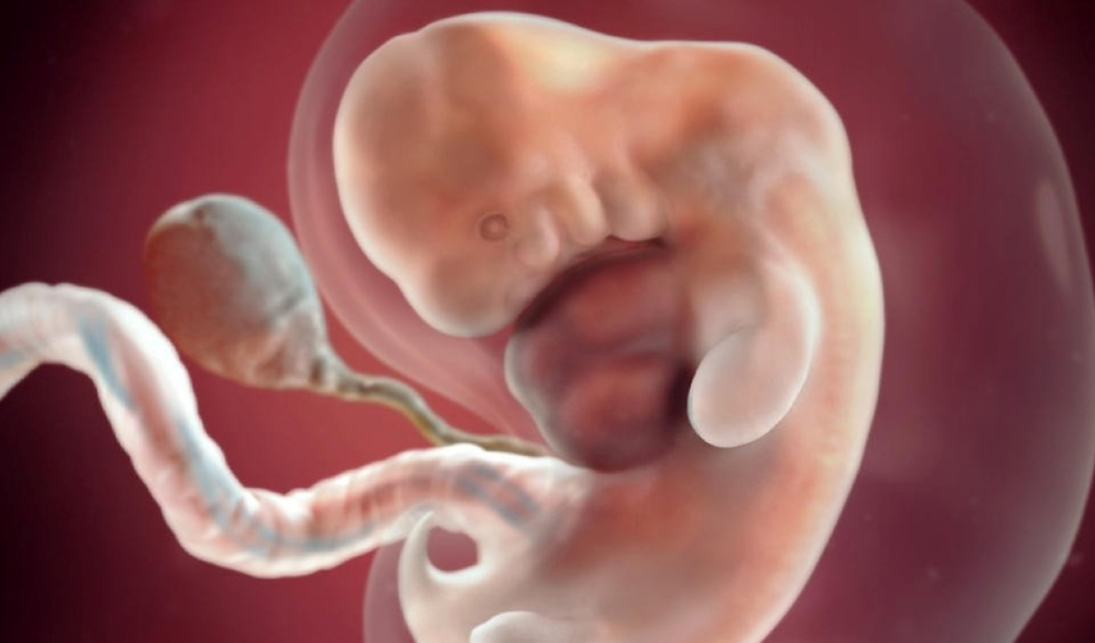

Sự phát triển của thai nhi trong 6 tuần đầu

Mách mẹ cách nhận biết dấu hiệu thai 6 tuần khỏe mạnh 1

Sau 6 tuần mang thai, thai nhi phát triển rất nhanh và các cơ quan bắt đầu thành hình

Tuần 6

• Thai nhi dài chưa tới 1 cm và không còn cái đuôi nhỏ. Đầu và trán vẫn rất to nhưng thân mình bé tí.

• Hình thành chóp mũi.

• Các ngón tay, ngón chân, chân, môi, mí mắt đang thành hình.

• Đôi mắt tiến gần hai bên thái dương hơn.

• Các van tim và những đường dẫn khí từ cổ họng đến phổi được hình thành.

• Xuất hiện những đường nét ở đầu các chi nơi mà sau này thành hình các ngón chân và ngón tay.

• Thai nhi nằm dạng chữ C, bắt đầu có vài cử động rất nhỏ, không chủ ý, di chuyển thấp thoáng bên trong tử cung là những dấu hiệu thai 6 tuần khỏe mạnh.

• Bé đã có thể gập cánh tay và cổ tay nhờ xương đã hình thành.